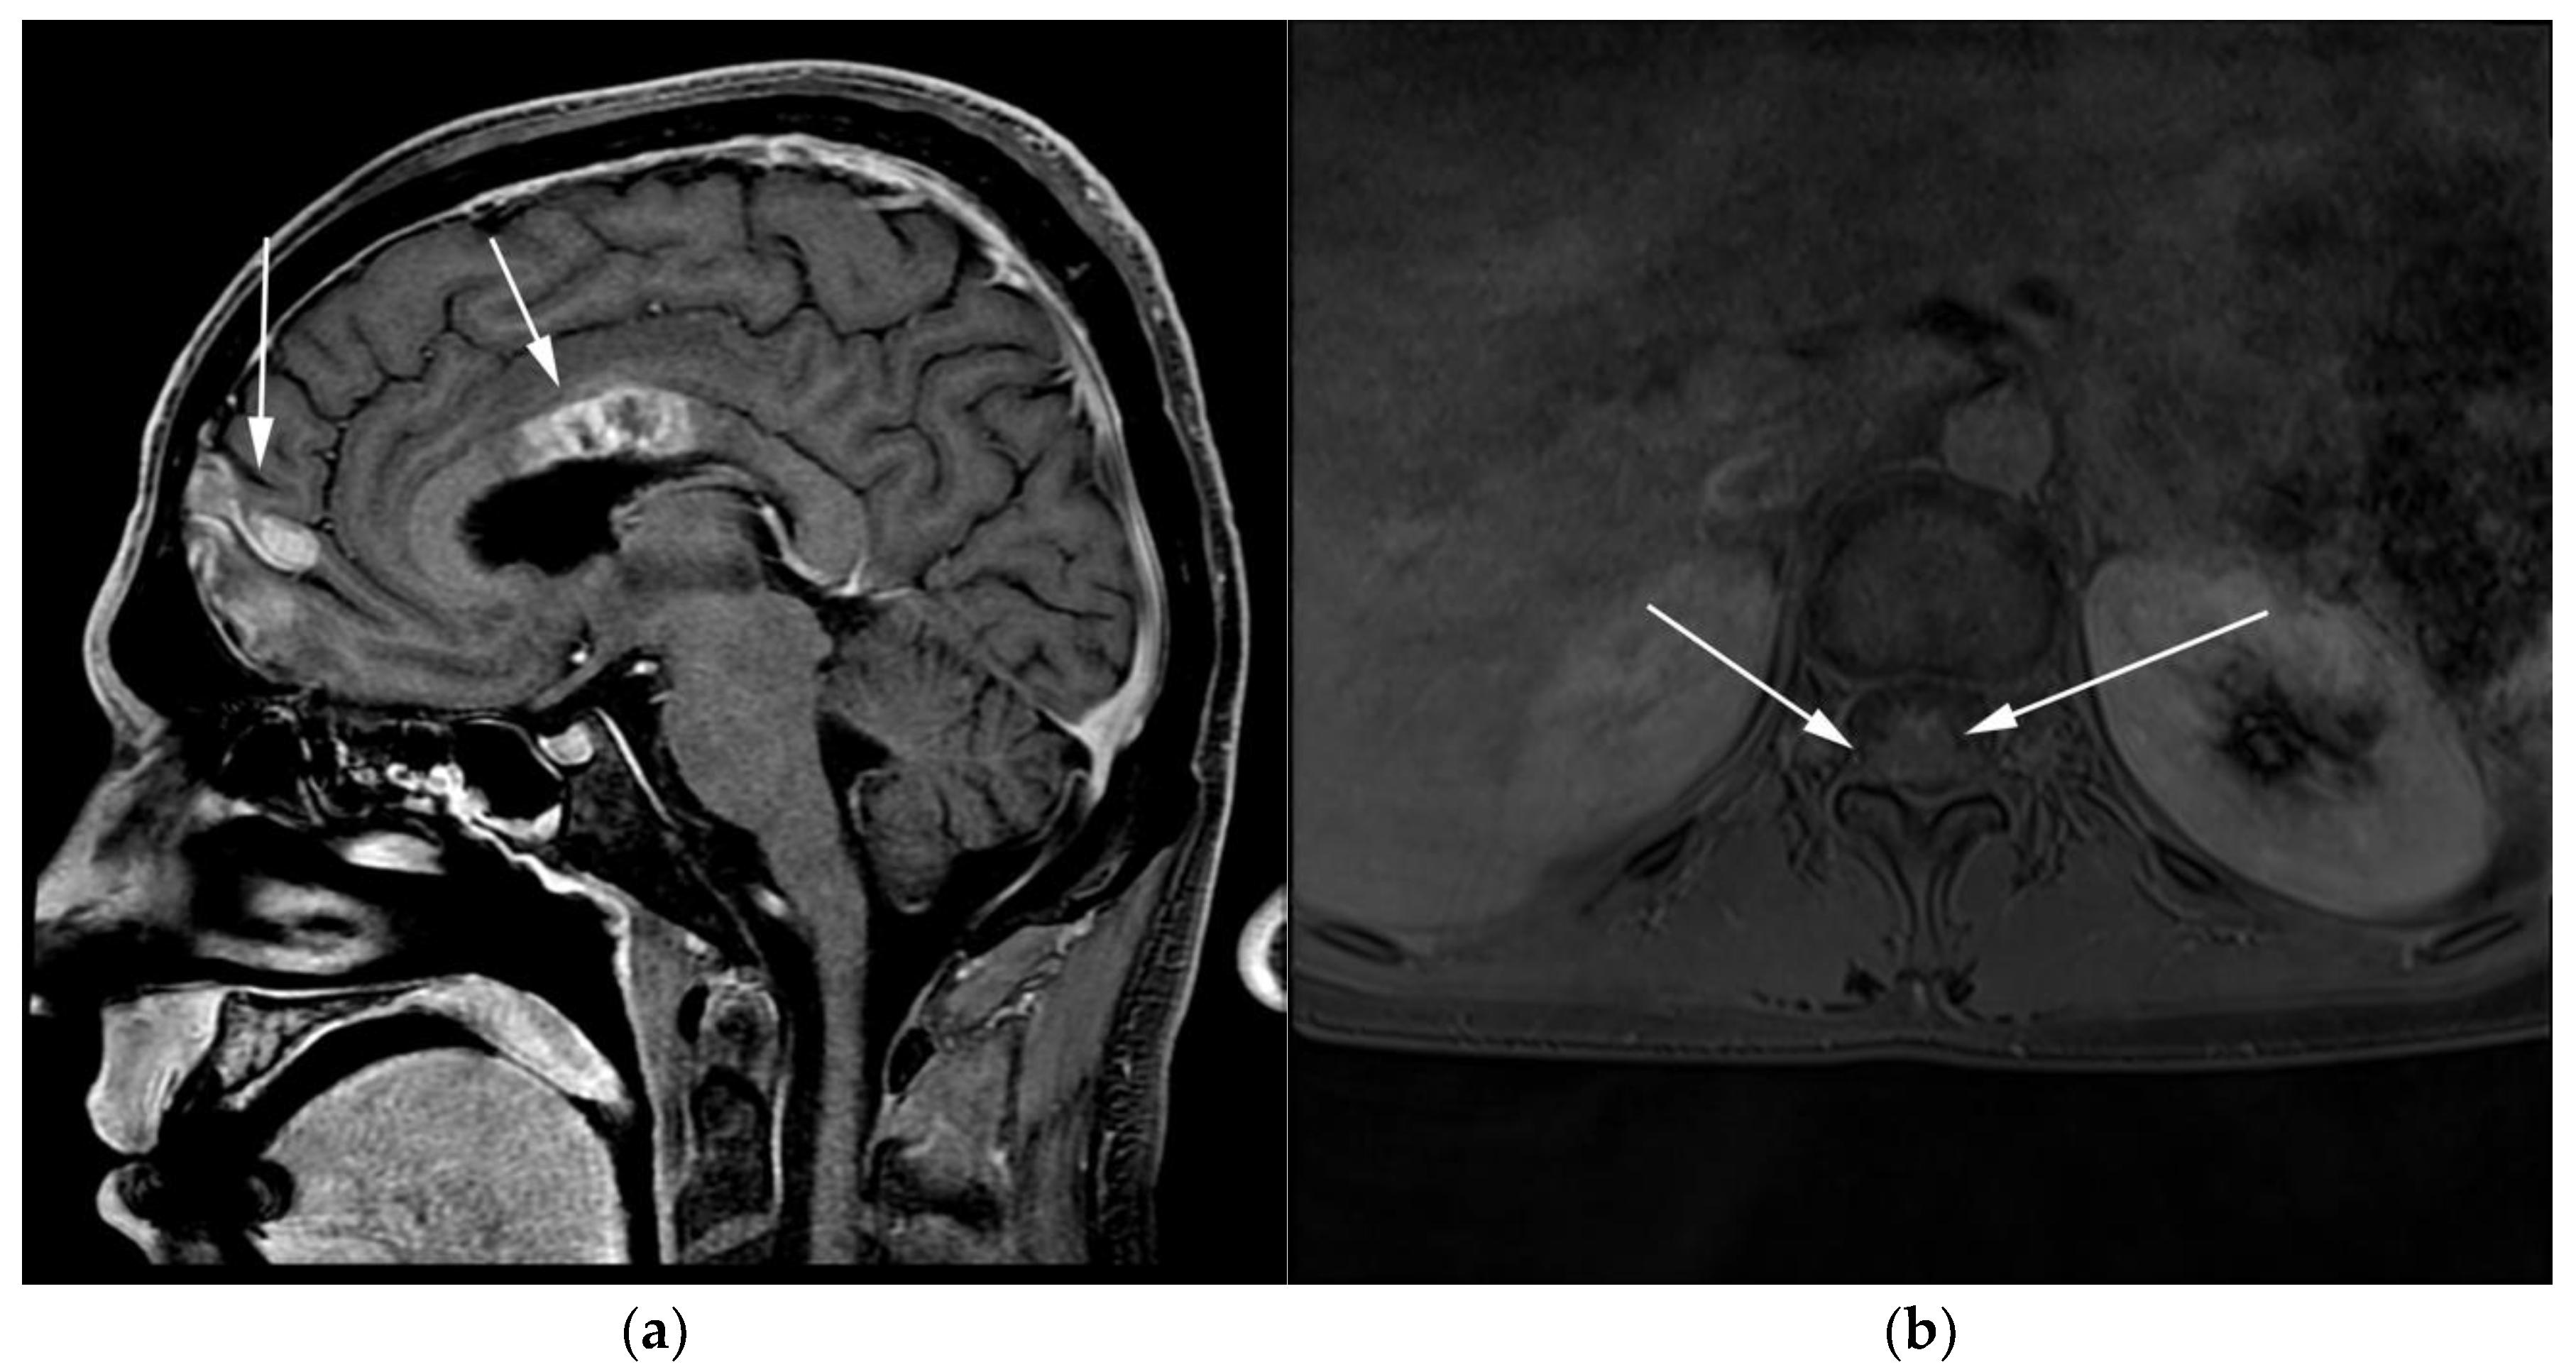

WM patients can also present with splenomegaly with or without focal lesions and lymphadenopathy typically within the axillary, retroperitoneal, and/or inguinal nodal stations (Figure 12). Cranial nerve deficits can be a manifestation of Bing–Neel syndrome, a rare CNS manifestation seen in WM disease [45,48,52,54]. In Bing–Neel syndrome, neurological symptoms can be directly related to infiltration by lymphoplasmacytic cells or indirectly result from the deposition of circulating IgM immunoglobulin on the brain parenchyma, spinal cord, or cranial or peripheral nerves (Figure 13). Additionally, 18F-FDG PET/CT plays an important role in monitoring therapeutic response after treatment initiation, especially with rituximab. WM patients tend to show elevated IgM levels, known as an IgM flare, which may mimic progressive disease. Imaging plays a pivotal role to differentiate between an IgM flare and true progression, thus obviating the need for repeated marrow biopsy [52]. Imaging may also help in excluding the development of myelodysplastic syndromes, acute leukemia, or DLBCL transformation [52].

Figure 12.

Lymphoplasmacytic lymphoma. (a) Axial FDG PET/CT in the same patient as Figure 8 shows hypermetabolic adenopathy within the bilateral iliac chain (white arrows). (b) Sagittal MRI T1-weighted image in the same patient shows a diffuse variegated appearance of the marrow consistent with marrow infiltration as that seen in multiple myeloma but without definite focal lytic lesions. Lymphoplasmacytic lymphoma combines features of both malignant lymphoma and multiple myeloma.

Figure 13.

Patient with known diagnosis of lymphoplasmacytic lymphoma (LPL). (a) Coronal T1 post-contrast of the brain image shows diffuse leptomeningeal enhancement (black arrows). (b) Axial MRI T1 post-contrast image of the lumbosarcal spine in the same patient shows diffuse epidural soft tissue thickening and enhancement of the cauda equina nerve roots (white arrows). (c) Microscopic examination of the lymph node shows effaced architecture by infiltrative diffuse sheets of atypical lymphoid cells with plasmacytoid morphology. Tumor cells are positive for CD20 and are monotypic, expressing kappa or lambda light chains. (Original magnification 400×, H&E stain). CNS involvement in is an extremely rare variant known as Bing–Neel syndrome (BNS).